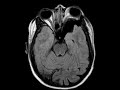

Sphenoid Wing Dysplasia

These images demonstrate deficiency of the left sphenoid wing with bulging of the meninges and peritemporal CSF into the posterolateral aspect of the orbit resulting in moderate left proptosis in this patient with a history of NF-1. There is asymmetric expansion of the left cerebral extra-axial spaces. No associated plexiform neurofibroma is identified. Findings are consistent with sphenoid wing dysplasia which is seen in less than 10% of patients with NF-1. Patients with this deformity may present with pulsating exophthalmos and diplopia. Management usually consist of surgical reconstruction.